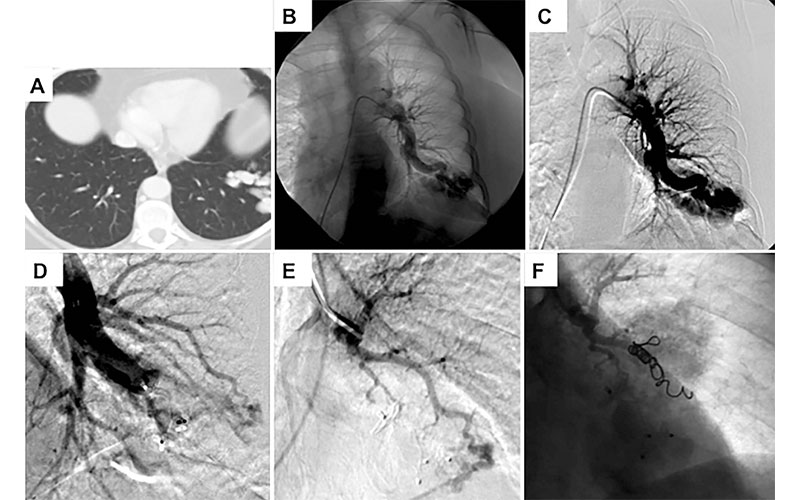

In the embolization procedure, a catheter is threaded from a large blood vessel in the leg to the site of the PAVM. A small coil is then inserted to block the PAVM. The procedure is highly effective, but the PAVMs will persist in some patients.